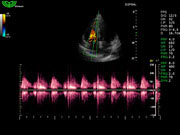

Система поддерживает СFM-режим, PW-режим, CW-режим, режим направленного энергетического потока, режим Color-M, панорамный режим, ECG, DICOM 3.0 и универсальные пакеты программ для кардиологии, сосудистого исследования и акушерства.

Режимы изображения: B, 2B, B/M, B/BC, CFM, PW, HPRF, PD, направленный PD, CW, режим Color M.

D3P64L 3.0МГц, фазированная решетка.

2.0МГц – 4.4МГц. Применения: кардиология, брюшная полость, акушерство. |